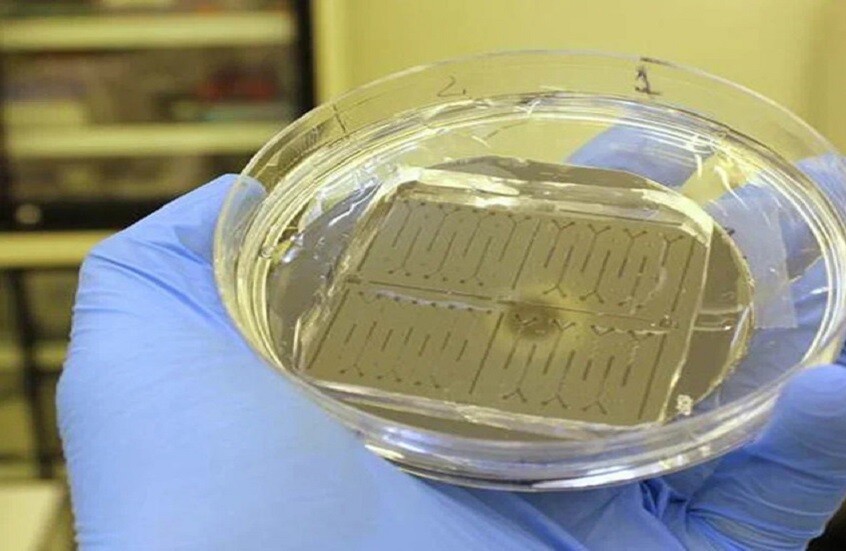

وقد ابتكر العلماء الروس شريحة ميكروفلويدية - جهاز صغير، يمر اللومينول (مركب كيميائي صيغته C8H7N3O2 قادر على توليد ضيائية كيميائية) ومحلول يحتوي على أنواع الأكسجين التفاعلية عبر قنوات دقيقة ذات بنية خاصة تعمل على تفتيت ومزج السوائل بسرعة فائقة. ثم يدخل اللومينول وأنواع الأكسجين التفاعلية إلى منطقة قياس التألق الضوئي. ويستغرق التفاعل نفسه جزءا من الثانية.